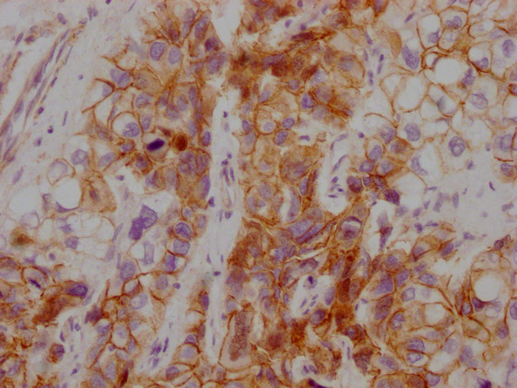

IHC image of CSB-MA907551 diluted at 1:100 and staining in paraffin-embedded human breast cancer performed on a Leica BondTM system. After dewaxing and hydration, antigen retrieval was mediated by high pressure in a citrate buffer (pH 6.0). Section was blocked with 10% normal goat serum 30min at RT. Then primary antibody (1% BSA) was incubated at 4°C overnight. The primary is detected by a Goat anti-mouse IgG polymer labeled by HRP and visualized using 0.05% DAB. -

IHC image of CSB-MA907551 diluted at 1:100 and staining in paraffin-embedded human liver cancer performed on a Leica BondTM system. After dewaxing and hydration, antigen retrieval was mediated by high pressure in a citrate buffer (pH 6.0). Section was blocked with 10% normal goat serum 30min at RT. Then primary antibody (1% BSA) was incubated at 4°C overnight. The primary is detected by a Goat anti-mouse IgG polymer labeled by HRP and visualized using 0.05% DAB